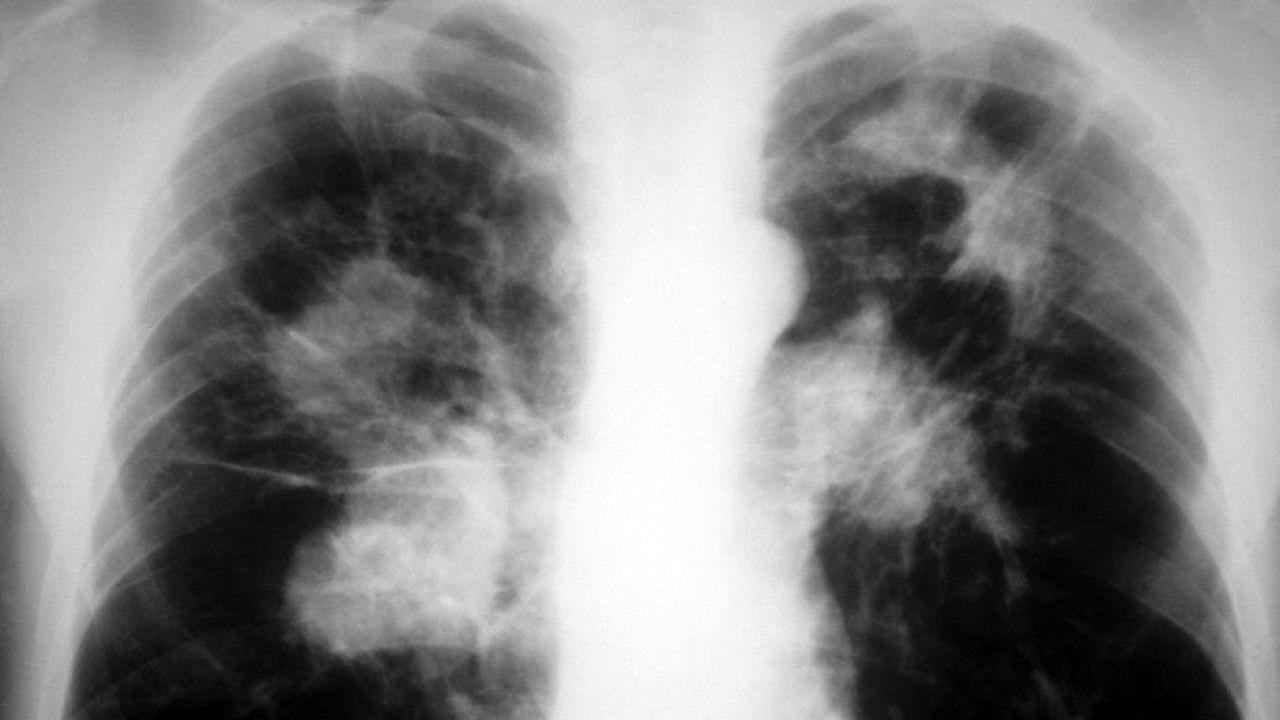

Tuberkuloza je bolest koja se danas dosta lako dijagnosticira. Važno je uzeti dobru anamnezu i obaviti pregled pacijenta, načiniti laboratorijske nalaze i RTG snimak pluća. Analiza biološkog materijala na tuberkuloznu klicu i dalje ostaje prva metoda za postavljanje dijagnoze - kazala je Feni šefica Klinike za plućne bolesti i tuberkulozu "Podhrastovi" KCUS-a prof. dr Belma Paralija, specijalista pneumoftiziolog, bronholog, povodom Sedmice borbe protiv tuberkuloze.

Tuberkuloza (TB) je zarazna bolest uzrokovana lako savijenim, tankim, aerobnim, nepokretnim, štapićastim uzročnikom, koji ne stvara spore, a pripada porodici Mycobacteriaceae. Od svih patogenih vrsta, koje pripadaju Mycobacterium tuberculosis (M. TB) kompleksu, najčešći i najznačajniji uzročnik bolesti kod ljudi je M. tuberculosis. Bolest može zahvatiti bilo koji organ, ali je najčešća lokalizacija u plućima.

Kada osoba oboli od tuberkuloze glavni simptomi su hronični kašalj, subfebrilne temperature, noćno znojenje, gubitak na težini, gubitak apetita, ponekad bol u prsima, a može se javiti i krvav iskašljaj.